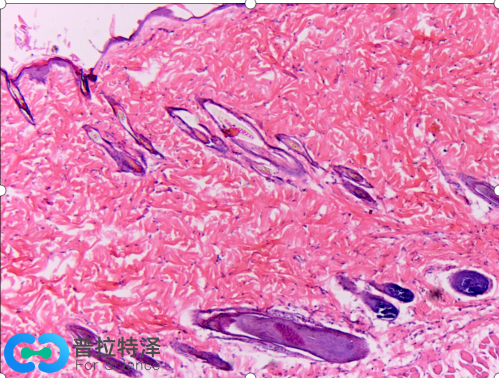

傳統的馬松染色使用四種染料,使組織切片呈現三種顏色,準確的稱呼是馬松三色染色法(Masson's trichrome stain)。第一種染料是蘇木精,配制成Weigert氏鐵蘇木精液,與HE染色相似,這里的蘇木精也是染細胞核,由于用的是鐵蘇木精,細胞核染色后不是經典HE染色的藍色,而是呈現暗灰黑色,這是第一色。第二種染料酸性品紅和第三種染料麗春紅配制成混合溶液,這兩種紅色染料染與HE染色中的伊紅相似,可以染細胞質為紅色,這是第二色。第四種染料是甲基藍(苯胺藍也可),染膠原纖維為藍色,這是第三色。經典的馬松染色效果與HE染色對比如下圖:

這是小鼠皮膚組織兩種病理染色圖片,左邊是馬松三色染色,右邊是HE染色。

右邊HE染色呈現藍色和紅色兩種顏色,而左邊馬松三色染色有灰黑色、紅色和藍色三種顏色,尤為明顯的是藍色。左圖中的大片藍色區域是皮膚上皮組織,結構較為疏松,含有較多的膠原纖維,被馬松三色染色法中的甲基藍染成藍色。這樣染色后,可以清晰地看到毛孔在上皮結蹄組織中的分布。因此,被染成藍色的細胞外基質(通常都含有膠原纖維)就能和細胞以及其他組織形成鮮明的對比,從而易于觀察。在某些病理狀態,如心肌梗死,肝硬化和腎纖維化等情況下,病變的細胞會被結締組織取代,用馬松染色能很好地發現病變部位,并能對病變進行定量的評估。因此,直到今天,馬松染色依然是組織學和病理學中活躍的染色方法,并出現了幾種改良的馬松染色,使得染色效果更加理想。

Masson染色預期結果:膠原纖維、粘液、軟骨呈藍色(如光綠液染色為綠色),胞漿、肌肉、纖維素、神經膠質呈紅色,核黑藍色。